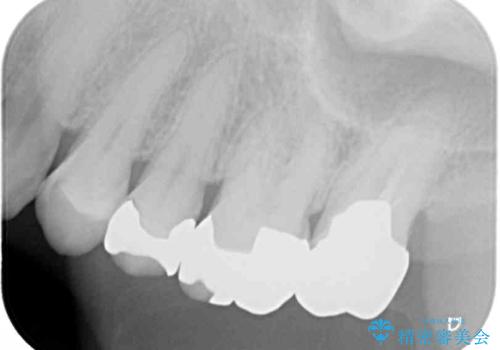

距離が近いこと以外、特に大きな問題は認められなかったため、ゴールドクラウン(PGAクラウン)にて補綴することとしました。

上の奥歯であることから、審美性よりも機能性を優先され、ゴールドクラウンを選択されました。

装着後の違和感など一切なく、見た目もほとんど気にならないとのことで、患者様には大変満足していただけました。